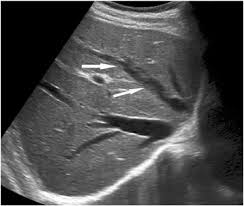

Chiasmata -mə-tə or chiasmas also chiasms 1. Esophageal varices are extremely dilated sub-mucosal veins in the lower third of the esophagus. Located in metro Denver northern Colorado and western Nebraska serving all of the Front Range our team consists of board-certified and fellowship-trained interventional radiologists. This results in hepatic congestion similar to Budd-Chiari syndrome and post-sinusoidal portal hypertension. The patients condition should be monitored throughout the procedure. They are most often a consequence of portal hypertension commonly due to cirrhosis. Toxic injury to liver sinusoids causes sloughing of endothelial cells that embolize to hepatic venules and cause eventual fibrosis of the venules. Coin in the Esophagus. There is no clear consensus regarding the number of occluded veins some authors claim that there should be at least one occluded hepatic vein 7 others state that there are no significant.

Carcinoma of the Colon. Budd-Chiari syndrome a blockage in one or more veins that carry blood from the liver back to the heart. And coumarin skin necrosis adrenal gland hemorrhage and infarction. Toxic injury to liver sinusoids causes sloughing of endothelial cells that embolize to hepatic venules and cause eventual fibrosis of the venules. Chiari malformation CM is a structural defect in the cerebellum characterized by a downward displacement of one or both cerebellar tonsils through the foramen magnum the opening at the base of the skull. Embolism and thrombosis of. La présence dune ou plusieurs affections prothrombotiques est fréquente La prise en charge repose sur un traitement anticoagulant précoce le traitement de l.